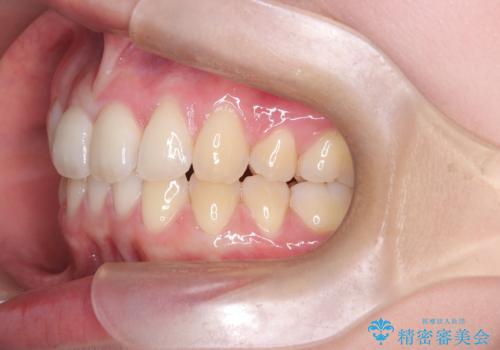

- 患者様は、上下の噛み合わせのバランスが悪く、特に上顎の前歯の突出を気にされて来院されました。診査の結果、下顎の歯並びに合わせて上顎を後方へ移動させる必要があると判断し、上顎の小臼歯2本を抜歯することを提案しました。目立たない矯正を希望されたため、**インビザライン(マウスピース矯正)**を選択。計画的にスペースを作りながら、バランスの取れた歯並びを目指しました。

治療はまず、上顎の小臼歯を2本抜歯し、そのスペースを利用して前歯を後方へ移動させました。インビザラインはアタッチメントを併用し、より効率的に歯を動かせるよう調整。定期的なチェックとアライナーの交換を続け、約3年かけて理想的な歯並びと噛み合わせを実現しました。治療後はリテーナーを使用し、安定した状態を維持。患者様からは「口元がスッキリし、横顔の印象も変わった」と嬉しいお声をいただきました。